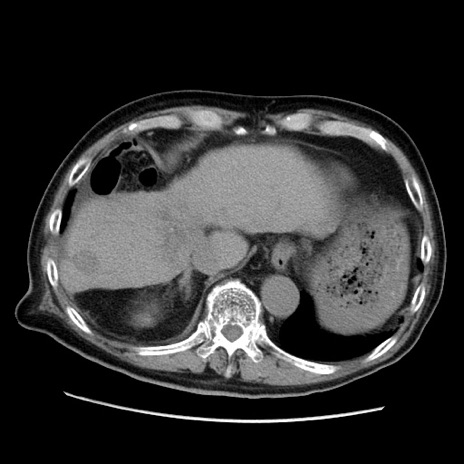

症例21(横断像)

【症例】70歳代男性

【主訴】腹痛

【現病歴】肝硬変・肝細胞癌にてかかりつけの方。約9時間前に食後より腹痛出現。症状が徐々に増悪し、嘔吐出現したため来院。

【既往歴】肝硬変、肝細胞癌(RFA、TACE後)

【身体所見】意識清明、表情苦悶様、BT 36℃、BP 129/78mmHg、P 88bpm、SpO2 97%(RA)、右上腹部から心窩部にかけて圧痛あり、反跳痛なし、筋性防御あり。

【データ】WBC 5800、CRP 0.16